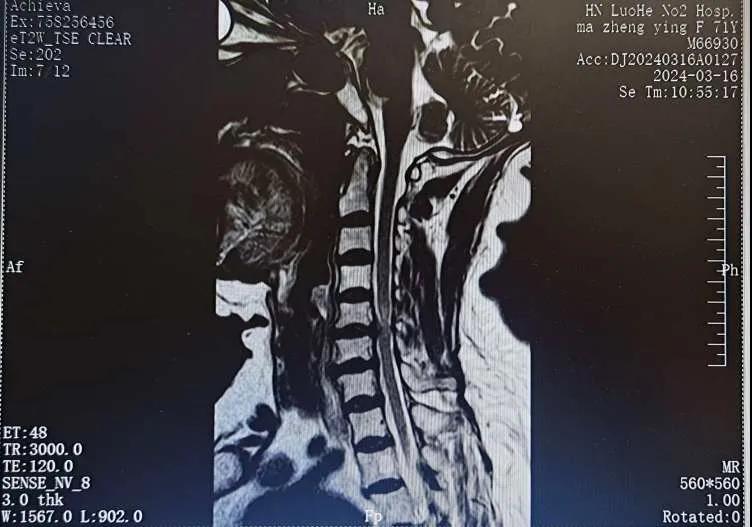

近日,70歲的馬阿姨,因摔傷后出現(xiàn)持續(xù)性頸部疼痛伴右側(cè)肢體無(wú)力、麻痛,影響日常生活。于是來(lái)到市二院神經(jīng)外科就診,經(jīng)檢查發(fā)現(xiàn):頸椎MR示:頸3/4、4/5、5/6、6/7椎間盤(pán)變性突出(中央型)并繼發(fā)性椎管變窄,頸椎退行性改變,頸5椎體水平頸髓水腫。神經(jīng)外科副主任劉沛濤根據(jù)患者癥狀、體征、影像學(xué)三者結(jié)合診斷為“脊髓型頸椎病”,考慮到患者癥狀逐漸加重、保守治療效果不佳等情況,建議盡快手術(shù)治療。